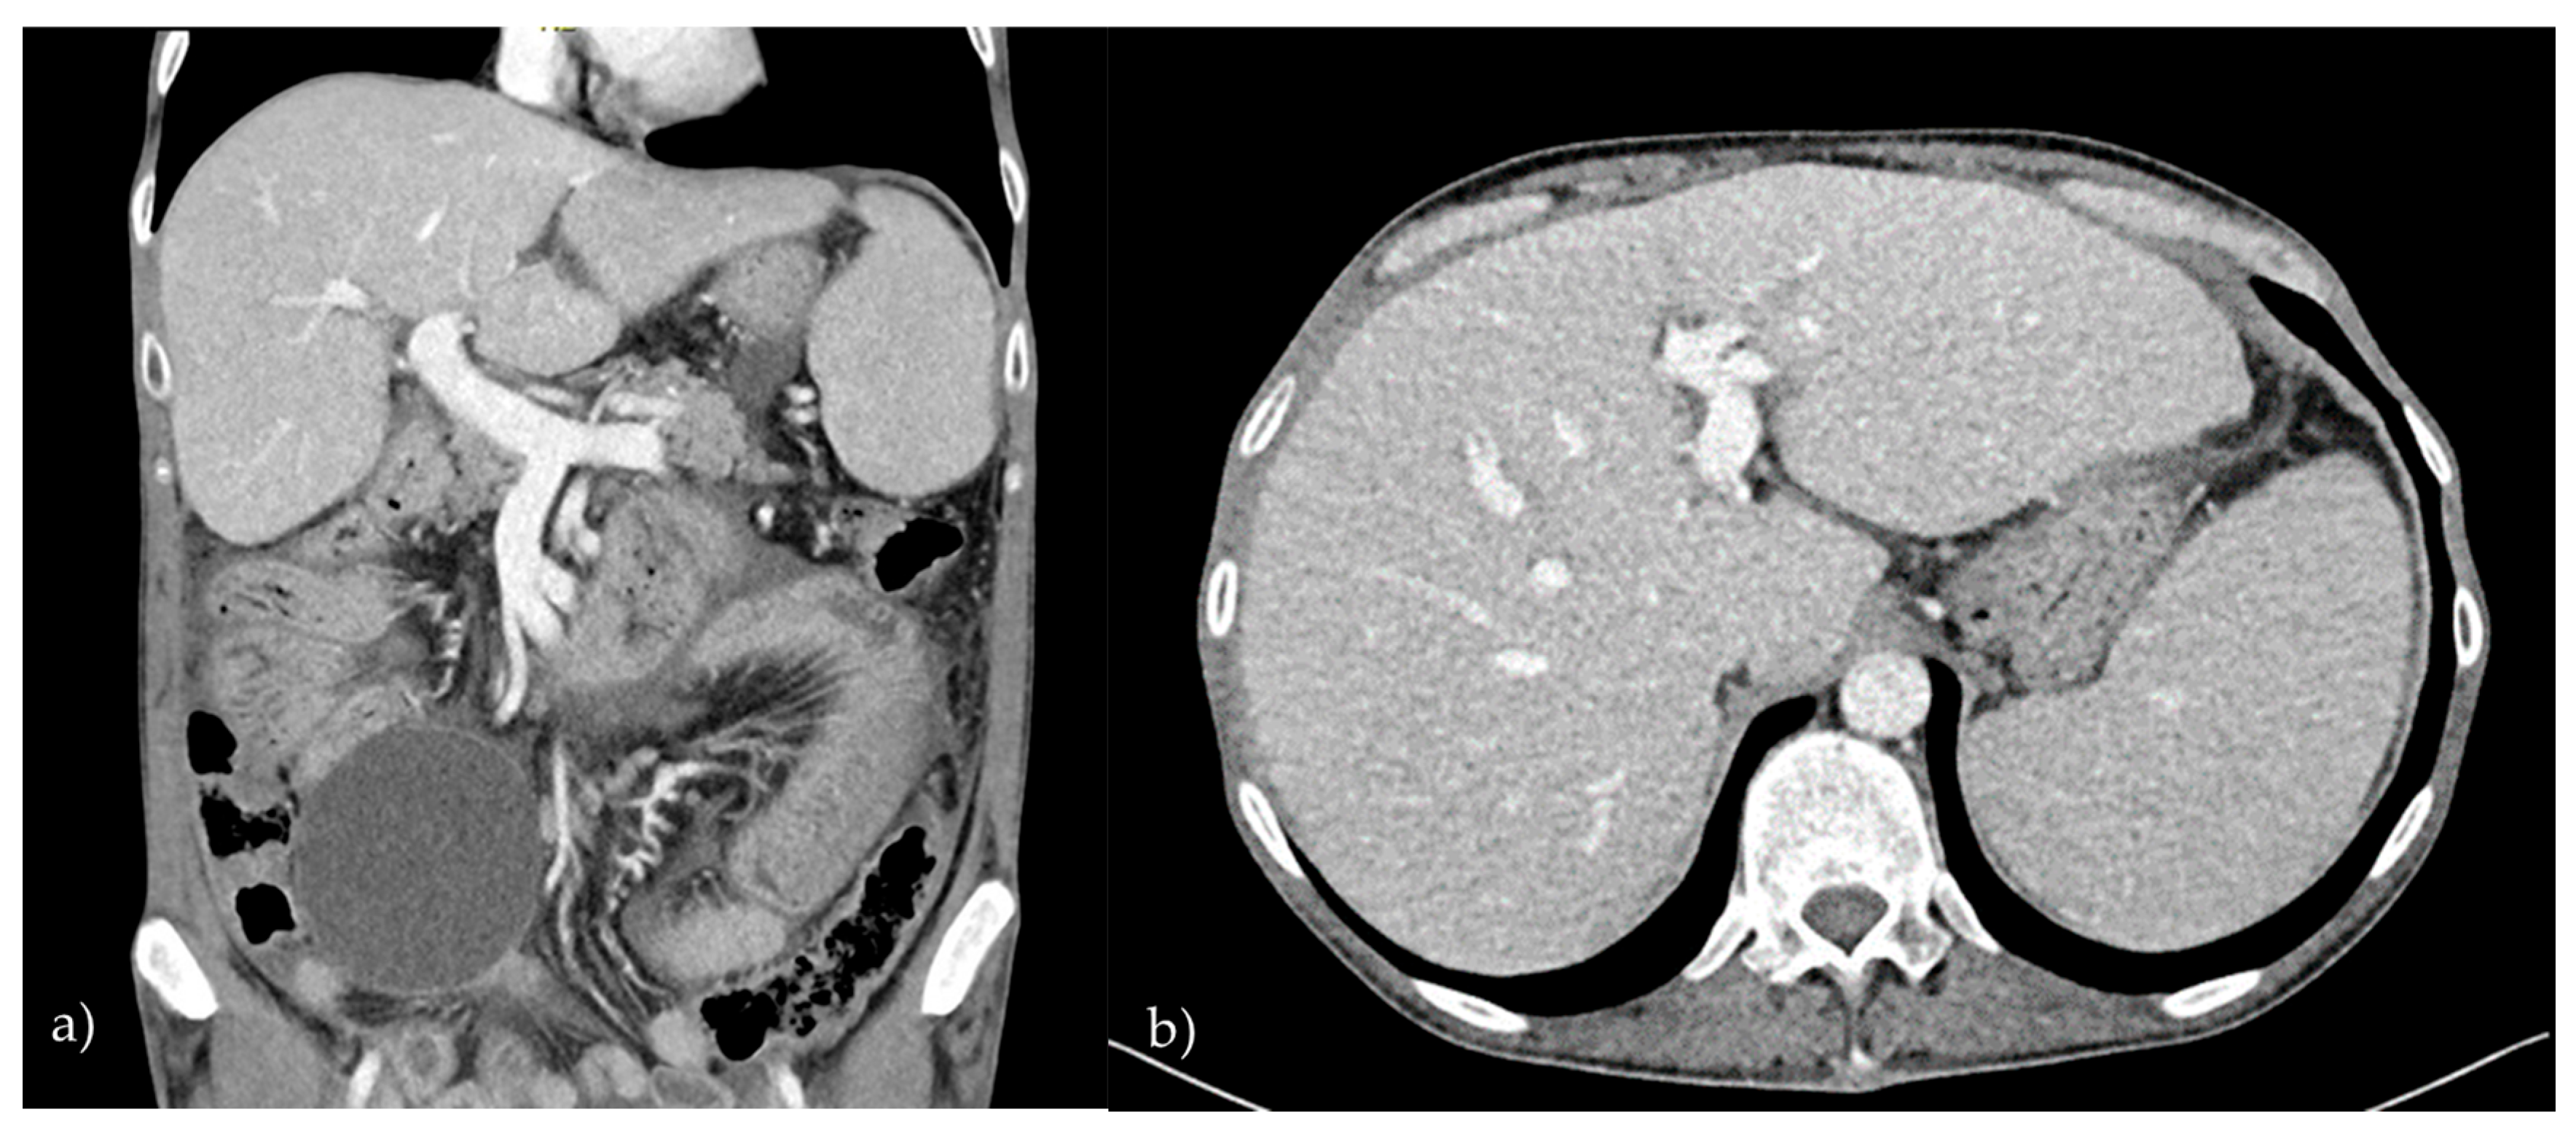

2.1. Patient 1

2.2. Patient 2